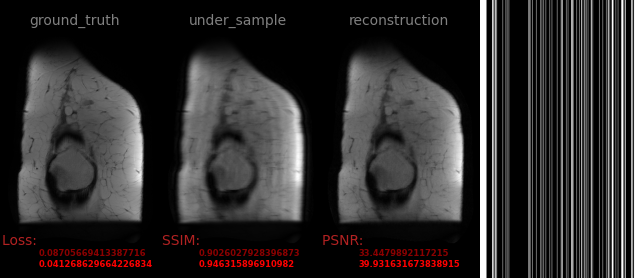

avs_b15

108.png